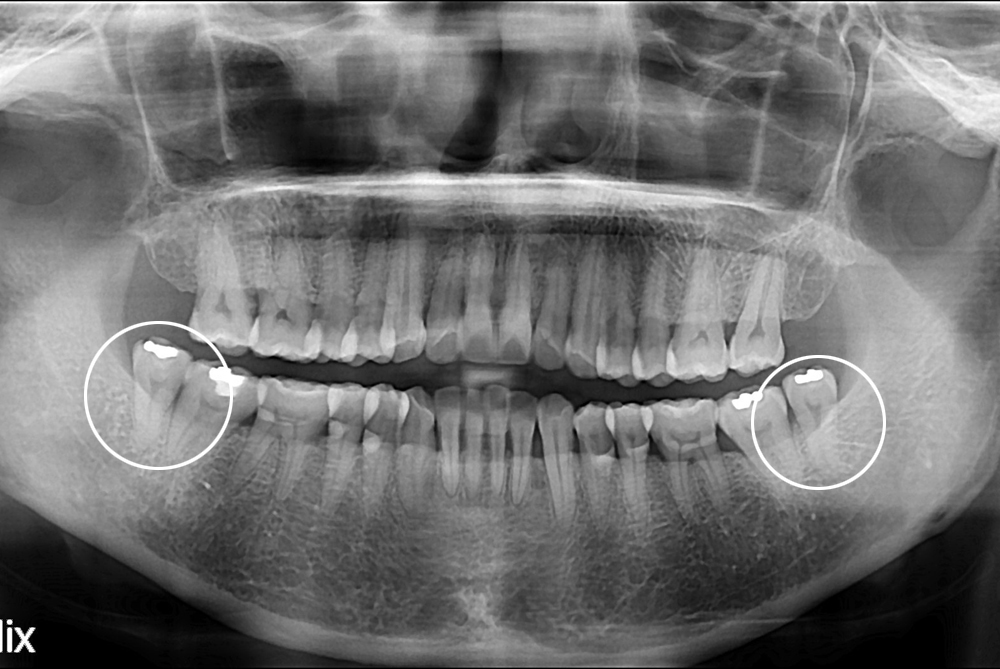

[사랑니] 난발치 사랑니 발치

치료전 : 2017-01-03